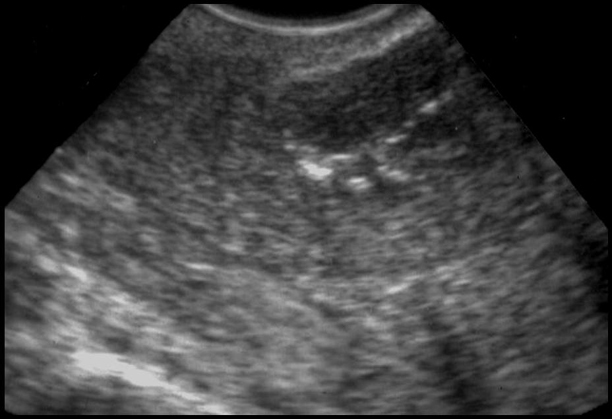

Métaplasie ostéoïde. Ossification en lamelle de la surface de l’endomètre. Antécédents de curetage ou d’endométrite. Calcifications visibles au niveau de la couche basale de l’endomètre.